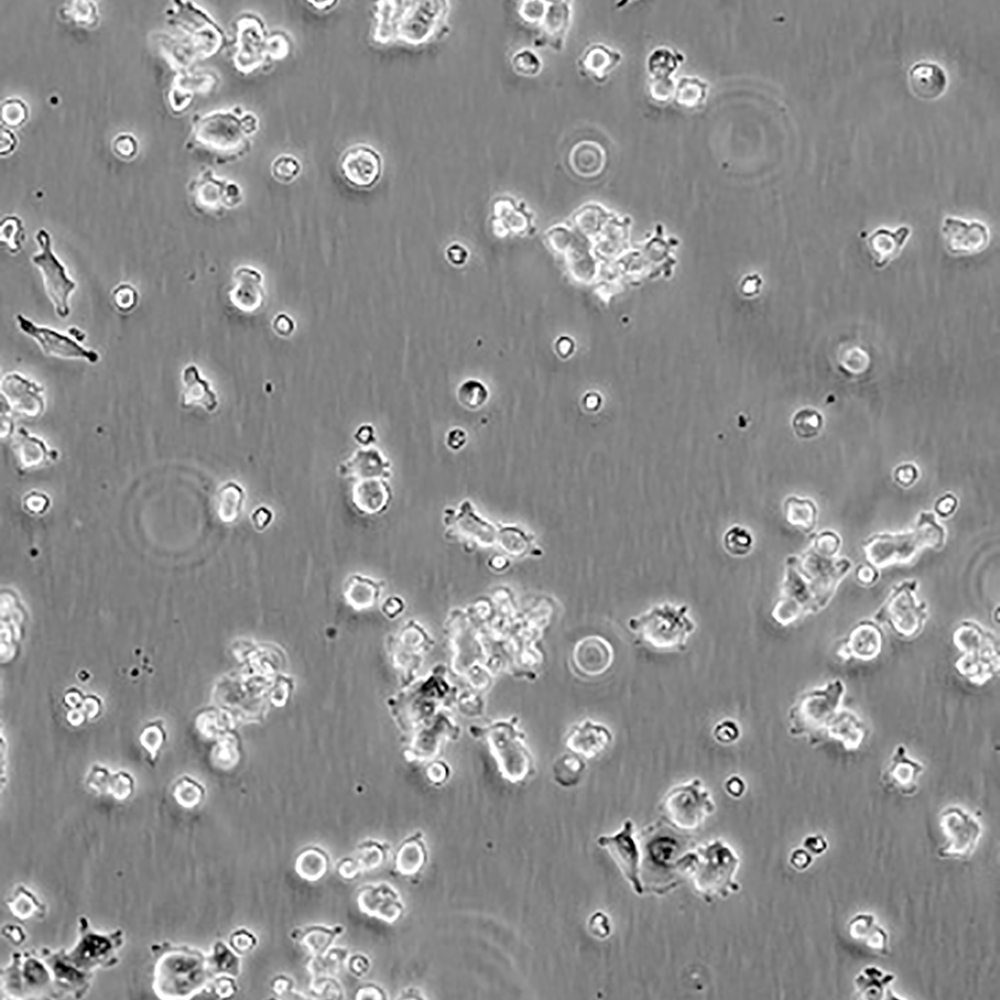

中文名稱 人肺腺癌細胞

組織來源 肺腺癌;男性

生長特性 貼壁

培養基 1640,90%;FBS,10%;雙抗。

培養條件 Atmosphere: Air, 95%; CO2, 5%。Temperature: 37℃